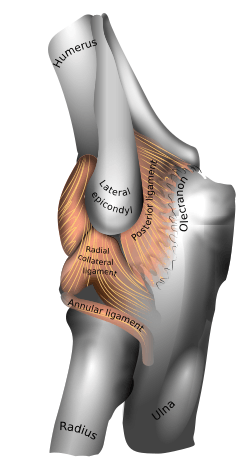

Left: anterior and ulnar collateral ligaments

Right: posterior and radial collateral ligaments

The elbow, like other joints, has ligaments on either side. These are triangular bands which blend with the joint capsule. They are positioned so that they always lie across the transverse joint axis and are, therefore, always relatively tense and impose strict limitations on abduction, adduction, and axial rotation at the elbow.[7]

The ulnar collateral ligament has its apex on the medial epicondyle. Its anterior band stretches from the anterior side of the medial epicondyle to the medial edge of the coronoid process, while the posterior band stretches from posterior side of the medial epicondyle to the medial side of the olecranon. These two bands are separated by a thinner intermediate part and their distal attachments are united by a transverse band below which the synovial membrane protrudes during joint movements. The anterior band is closely associated with the tendon of the superficial flexor muscles of the forearm, even being the origin of flexor digitorum superficialis. The ulnar nerve crosses the intermediate part as it enters the forearm.[7]

The radial collateral ligament is attached to the lateral epicondyle below the common extensor tendon. Less distinct than the ulnar collateral ligament, this ligament blends with the annular ligament of the radius and its margins are attached near the radial notch of the ulna.[7]